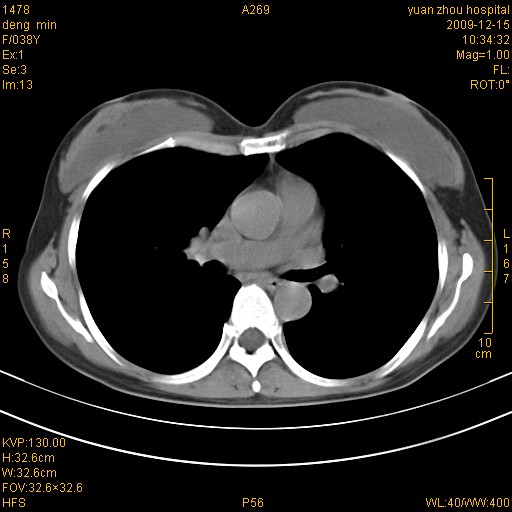

标题: CT23919:F38Y 咳嗽月余 [打印本页]

标题: CT23919:F38Y 咳嗽月余

右肺中下叶、左肺上叶舌段及左肺下叶支气管扩张合并感染。